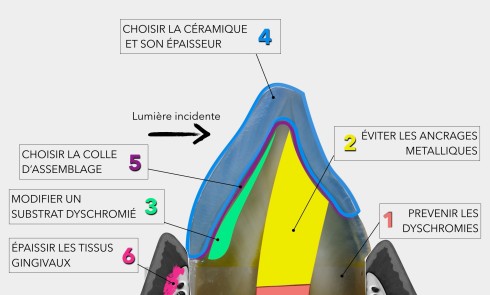

En effet, les MIH sont des hypominéralisations amélaires qui ont la particularité de débuter non pas en subsurface, mais au niveau de la jonction amélo-dentinaire [3]. Elles s’étendent dans l’épaisseur de l’émail en fonction de leur sévérité. Les MIH légères (blanches) présentent donc une localisation interne non accessible par le protocole standard d’érosion. Ainsi, le principe de traitement par érosion/infiltration en profondeur des MIH n’est pas, comme dans les deux premiers cas, d’améliorer l’infiltration dans le corps de la lésion, mais d’aller rechercher par sablage ou par fraisage le plafond de la lésion avant de l’infiltrer.